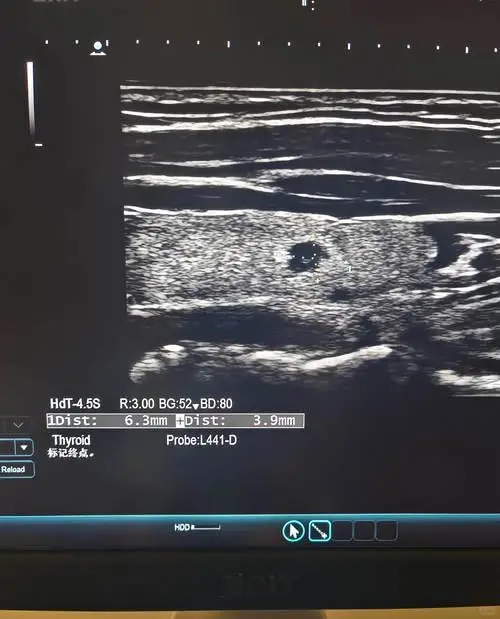

8. 甲状腺彩超(推荐加入)

检查甲状腺结节、囊肿、肿大、肿瘤等

建议人群: 女性、长期处于高压状态、有结节家族史者